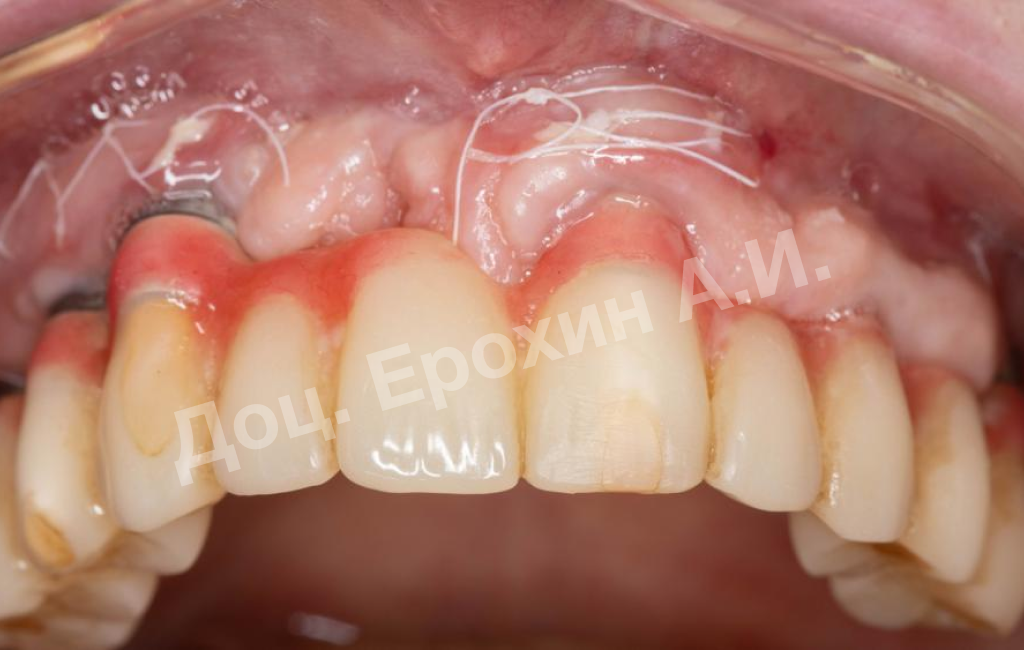

В результате, спустя 10 лет мы видим, что единственная часть десны в области имплантации, не затронутая рецессиями, — это зона, где была проведена трансплантация десневого фрагмента. С целью стабилизации имеющихся имплантатов на повторном приеме была проведена вестибулопластика по Кларку с фиксацией мягкотканных мукотомов, фрагментов эпителия с неба, зафиксированных швами.

В данном клиническом случае мы можем наблюдать эффект так называемого наползающего прикрепления (creeping attachment), когда десна после удаления момента натяжения начинает сама наплывать на ранее оголенные корни зубов и имплантаты.

На фото видно, что в первом сегменте с 2.5-3 мм оголение корня осталось меньше 1 мм, в области имплантата 21 рецессия самоустранилась, а в области имплантата 26 рецессия до операции была 4.5 мм, а после сократилась до 2 мм.